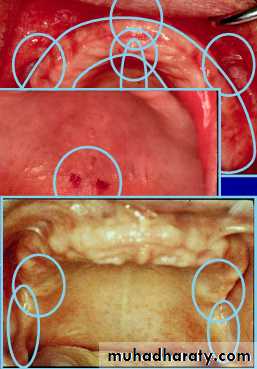

Anatomy of Edentulous Maxilla

Labial and buccal frenum and sulcus

Ridge, Cuspid eminence, Malar bone

Incisive papillaMidpalatine suture

Fovia palatinusHamular notch

Pteregmandibular raphe or ligamentAnatomy of Edentulous Maxilla

Primary stress bearing areas::::::: horizontal portion of hard palate (1).

Secondary stress bearing areas::

::::: ridge crest (2).

Non stress bearing areas::

:::: ridge slopes (n/c).Anatomy of Edentulous Mandible

Retromolar padAnatomy of Edentulous Mandible

Primary stress bearing area;

::: buccal shelf

Secondary stress bearing area;

::: residual ridgeNon stress bearing area;

::: Labial & lingual inclines (n/c)Preliminary Impression of Maxillary Arch